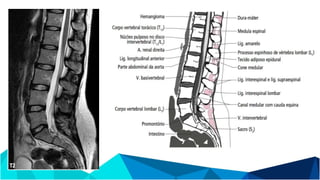

ANATOMIA